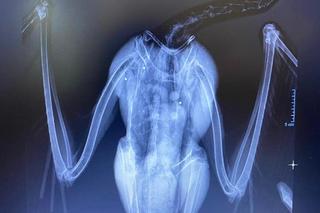

Na Podkarpaciu ktoś strzela do bocianów jak do żywych tarcz. W ostatnich dniach do Fundacji Ada w Przemyślu trafiło kilkanaście ptaków z ranami postrzałowymi. Jednego nie udało się uratować, był postrzelony aż 12 razy! Śrut zniszczył jego wątrobę, płuco, skrzydło i miednicę. Postrzelony bocian zazwyczaj kończy jako kaleki ptak, który już do końca życia nie będzie mógł żyć na wolności. Wszystkiemu winien jest człowiek.

Ostatnio fundacja zajmowała się trzema bocianami. Jednego z nich nie udało się uratować. Został postrzelony 12 razy.

- Ktoś sobie z tego bociana po prostu zrobił żywą tarczę. Miał w ciele mnóstwo śrutów, mnóstwo złamań. Niektóre były w okolicach płuc, serca - zaznacza lekarz weterynarii Angelika Szkolnik.

Obecnie pod skrzydła Fundacji trafiło kilka bocianów, każdy z ranami postrzałowymi. Każdy bezmyślnie skrzywdzony przez człowieka. Większość z nich jest w takim stanie, że już nigdy nie wzbije się w powietrze Na zawsze zostaną w bocianim szpitalu, który stworzyła Fundacja Ada. Ten znajduje się we Fredropolu nieopodal Przemyśla. Co roku trafia około 80 rannych ptaków. 60% z nich to bociany, a większość bocianów to niestety ofiary śrutu.